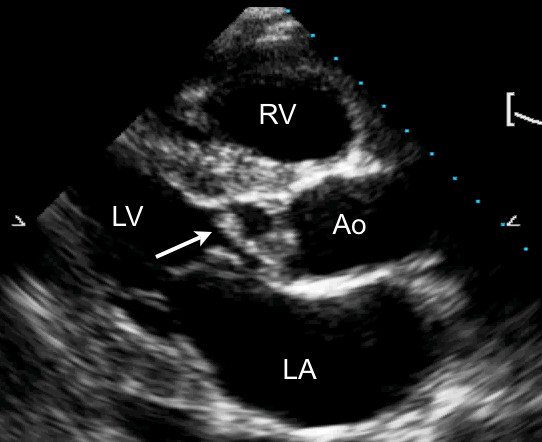

On cardiac exam, you note a systolic murmur at the right upper sternal border. The echo tech is rolling the machine by so you grab it and take a look: